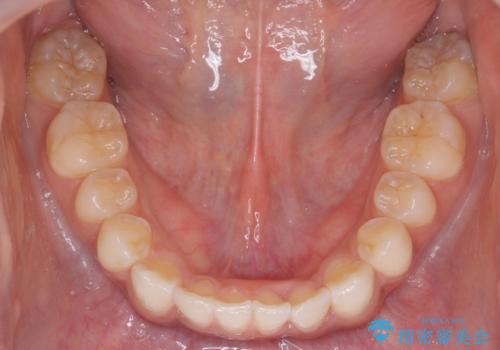

前歯のがたつき 1年かからず治療 マウスピース矯正

- 前歯のがたつきを主訴に来院。

インビザラインで歯を抜かずに並べました。

マウスピースの延長(リファインメント)もなく、短期間で綺麗に並びました。